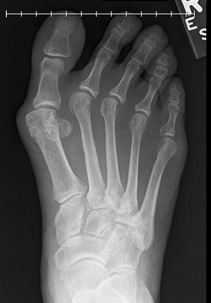

We take so much for granted in life. Like walking with a steady gait without pain. Like being able to stand for long periods of time without discomfort. Like wearing whatever footwear we like. I knew these pleasures until I developed a huge bunion on my right foot that was so disruptive it dislocated the other four toes on that foot! Pain was a daily occurrence that affected my work and lifestyle. When a person's quality of life is compromised, it's time to act. I knew I needed foot surgery.

Being a surgical nurse for over forty years I know how important it is to choose the surgeon who is absolutely the most qualified to do what needs to be done. You want to go to the best. I was so fortunate to know Dr. Leavitt on a professional level. His knowledge and skill have made him an expert in foot reconstructive surgery. I knew he could and would fix my foot. I went to the best for my surgery and I'm so glad I did.